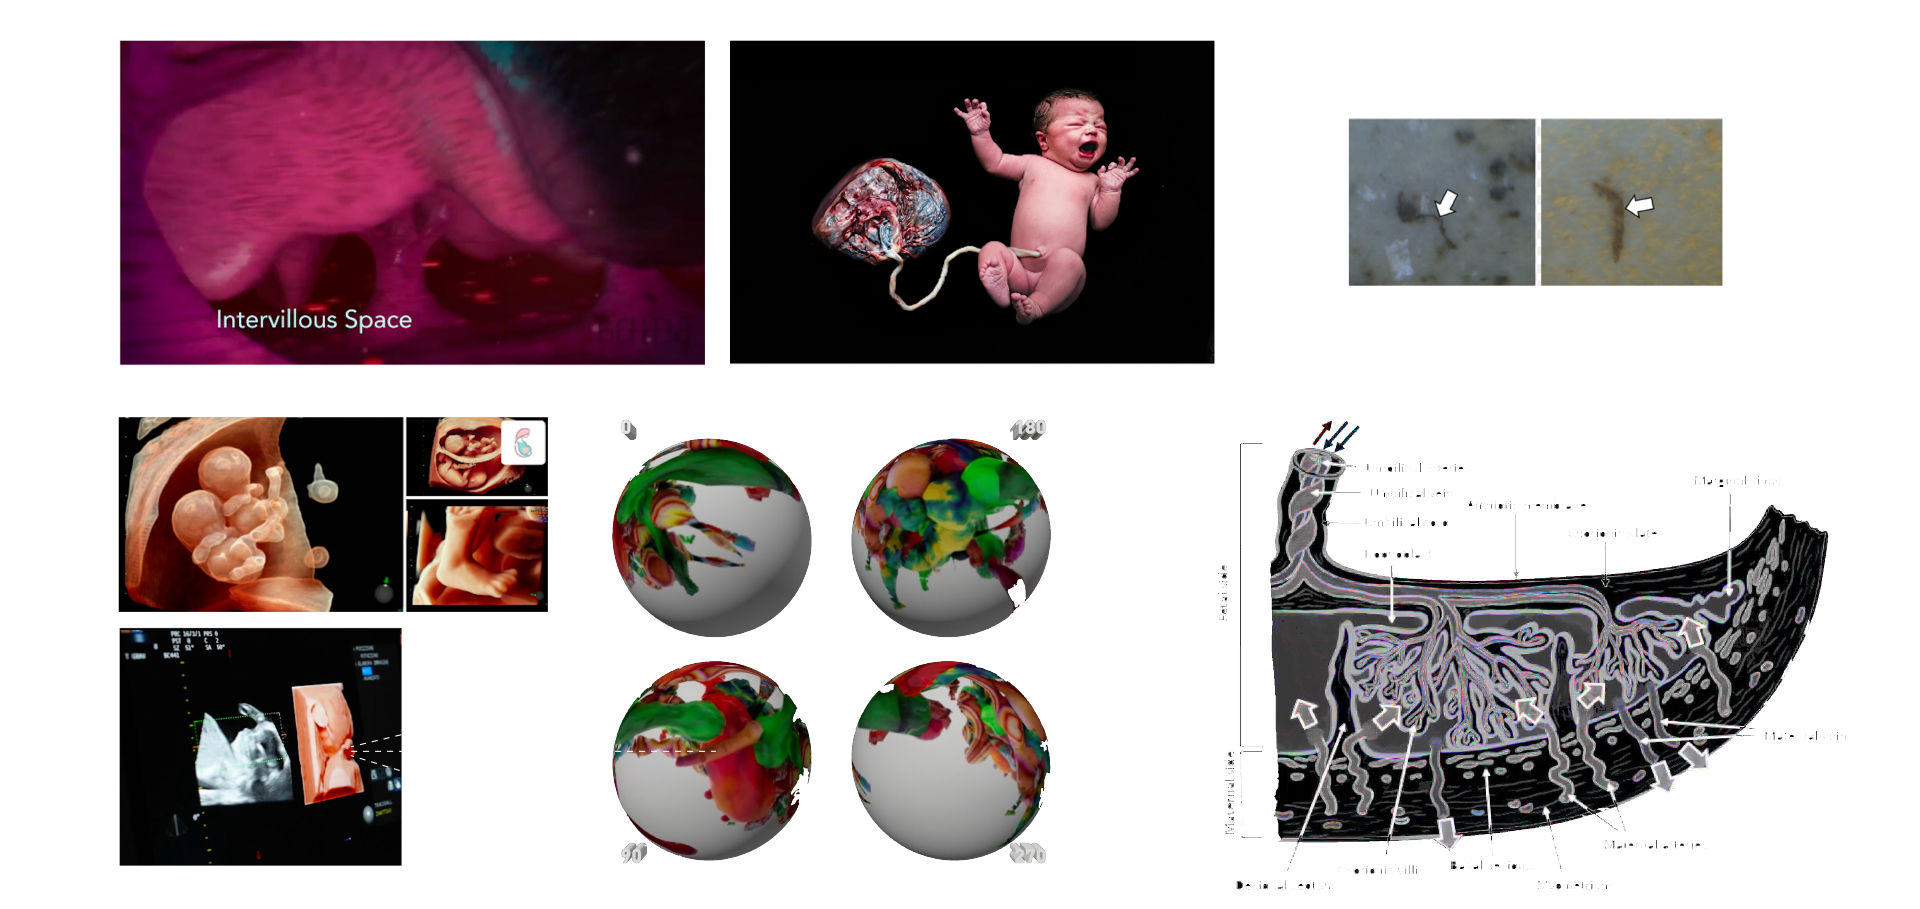

MICROPLASTICS (MPS) ARE DEFINED AS PLASTIC PARTICLES SMALLER THAN 5 MM. THEY HAVE BEEN FOUND ALMOST EVERYWHERE THEY HAVE BEEN SEARCHED FOR AND RECENT DISCOVERIES HAVE ALSO DEMONSTRATED THEIR PRESENCE IN HUMAN PLACENTA, BLOOD, MECONIUM, AND BREASTMILK, BUT THEIR LOCATION AND TOXICITY TO HUMANS HAVE NOT BEEN REPORTED TO DATE. THE AIM OF THIS STUDY WAS TWOFOLD:

1. TO LOCATE MPS WITHIN THE INTRA/EXTRACELLULAR COMPARTMENT IN HUMAN PLACENTA.

2. TO UNDERSTAND WHETHER THEIR PRESENCE AND LOCATION ARE ASSOCIATED WITH POSSIBLE STRUCTURAL CHANGES OF CELL ORGANELLES. USING VARIABLE PRESSURE SCANNING ELECTRON MICROSCOPY AND TRANSMISSION ELECTRON MICROSCOPY, MPS HAVE BEEN LOCALIZED IN TEN HUMAN PLACENTAS. IN THIS STUDY, WE DEMONSTRATED FOR THE FIRST TIME THE PRESENCE AND LOCALIZATION IN THE CELLULAR COMPARTMENT OF FRAGMENTS COMPATIBLE WITH MPS IN THE HUMAN PLACENTA AND WE HYPOTHESIZED A POSSIBLE CORRELATION BETWEEN THEIR PRESENCE AND IMPORTANT ULTRASTRUCTURAL ALTERATIONS OF SOME INTRACYTOPLASMIC ORGANELLES (MITOCHONDRIA AND ENDOPLASMIC RETICULUM). THESE ALTERATIONS HAVE NEVER BEEN REPORTED IN NORMAL HEALTHY TERM PREGNANCIES UNTIL TODAY. THEY COULD BE THE RESULT OF A PROLONGED ATTEMPT TO REMOVE AND DESTROY THE PLASTIC PARTICLES INSIDE THE PLACENTAL TISSUE. THE PRESENCE OF VIRTUALLY INDESTRUCTIBLE PARTICLES IN TERM HUMAN PLACENTA COULD CONTRIBUTE TO THE ACTIVATION OF PATHOLOGICAL TRAITS, SUCH AS OXIDATIVE STRESS, APOPTOSIS, AND INFLAMMATION, CHARACTERISTIC OF METABOLIC DISORDERS UNDERLYING OBESITY, DIABETES, AND METABOLIC SYNDROME AND PARTIALLY ACCOUNTING FOR THE RECENT EPIDEMIC OF NON-COMMUNICABLE DISEASES.

1. TO LOCATE MPS WITHIN THE INTRA/EXTRACELLULAR COMPARTMENT IN HUMAN PLACENTA.

2. TO UNDERSTAND WHETHER THEIR PRESENCE AND LOCATION ARE ASSOCIATED WITH POSSIBLE STRUCTURAL CHANGES OF CELL ORGANELLES. USING VARIABLE PRESSURE SCANNING ELECTRON MICROSCOPY AND TRANSMISSION ELECTRON MICROSCOPY, MPS HAVE BEEN LOCALIZED IN TEN HUMAN PLACENTAS. IN THIS STUDY, WE DEMONSTRATED FOR THE FIRST TIME THE PRESENCE AND LOCALIZATION IN THE CELLULAR COMPARTMENT OF FRAGMENTS COMPATIBLE WITH MPS IN THE HUMAN PLACENTA AND WE HYPOTHESIZED A POSSIBLE CORRELATION BETWEEN THEIR PRESENCE AND IMPORTANT ULTRASTRUCTURAL ALTERATIONS OF SOME INTRACYTOPLASMIC ORGANELLES (MITOCHONDRIA AND ENDOPLASMIC RETICULUM). THESE ALTERATIONS HAVE NEVER BEEN REPORTED IN NORMAL HEALTHY TERM PREGNANCIES UNTIL TODAY. THEY COULD BE THE RESULT OF A PROLONGED ATTEMPT TO REMOVE AND DESTROY THE PLASTIC PARTICLES INSIDE THE PLACENTAL TISSUE. THE PRESENCE OF VIRTUALLY INDESTRUCTIBLE PARTICLES IN TERM HUMAN PLACENTA COULD CONTRIBUTE TO THE ACTIVATION OF PATHOLOGICAL TRAITS, SUCH AS OXIDATIVE STRESS, APOPTOSIS, AND INFLAMMATION, CHARACTERISTIC OF METABOLIC DISORDERS UNDERLYING OBESITY, DIABETES, AND METABOLIC SYNDROME AND PARTIALLY ACCOUNTING FOR THE RECENT EPIDEMIC OF NON-COMMUNICABLE DISEASES.